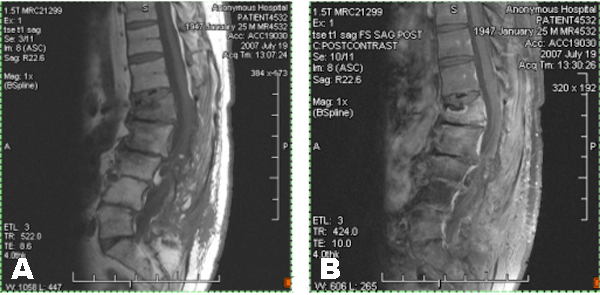

Figure 2: (A-B) Sagittal T1, (A) and T1 fat-saturated post-gadolinium, (B) images of the lumbar spine performed seven weeks later demonstrate marked improvement in previously noted vertebral body and disc space signal abnormalities, consistent with resolving osteomyelitis/discitis. There has also been interval decrease in epidural phlegmon, with minimal persistent epidural enhancement. Interval compression fracture involving the L1 vertebral body was noted, with anterior wedging and Gibbus deformity.